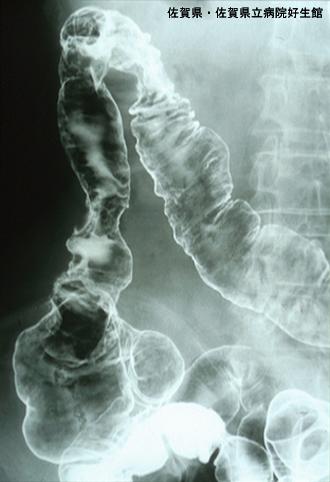

A case of phlebosclerotic colitis without calcification of the mesenteric vein.

Saga Pref., Saga Prefectural Hospital Koseikan (Dr.下田ら)

Inflammatory or ulcerative disease / lesions/phlebosclerotic colitis

Large intestine(Colon)/More than one of the above

X-ray